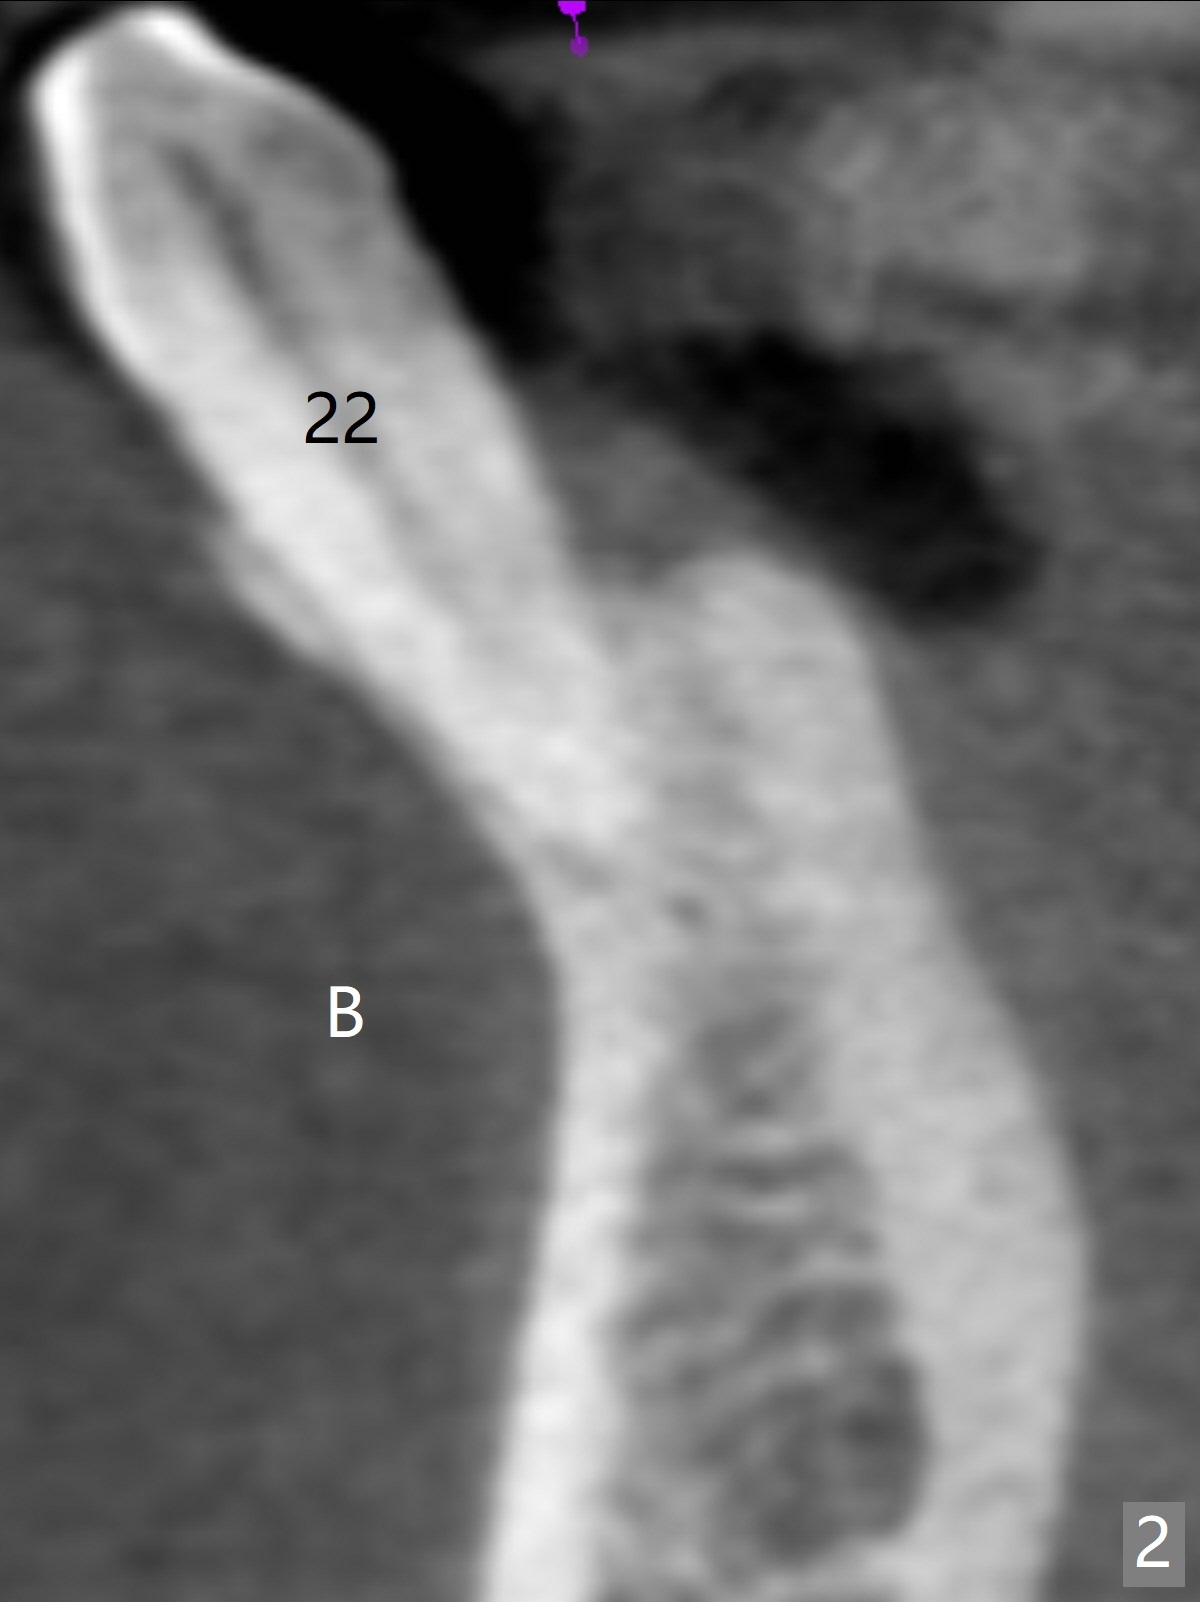

A 44-year-old woman will return for #22/23 (fusion) extraction and implant 2.5 months after one at #25 (Fig.1). If the mesiodistal width of the extraction socket(s) is not particularly wide, one implant will be placed. The tooth #22 seems to be buccally positioned (Fig.2 B). After extraction (Fig.3 black area), initiate osteotomy lingually (red line). Since the spongy bone is not wide buccolingually, a 3 mm implant appears to be appropriate (Fig.4).